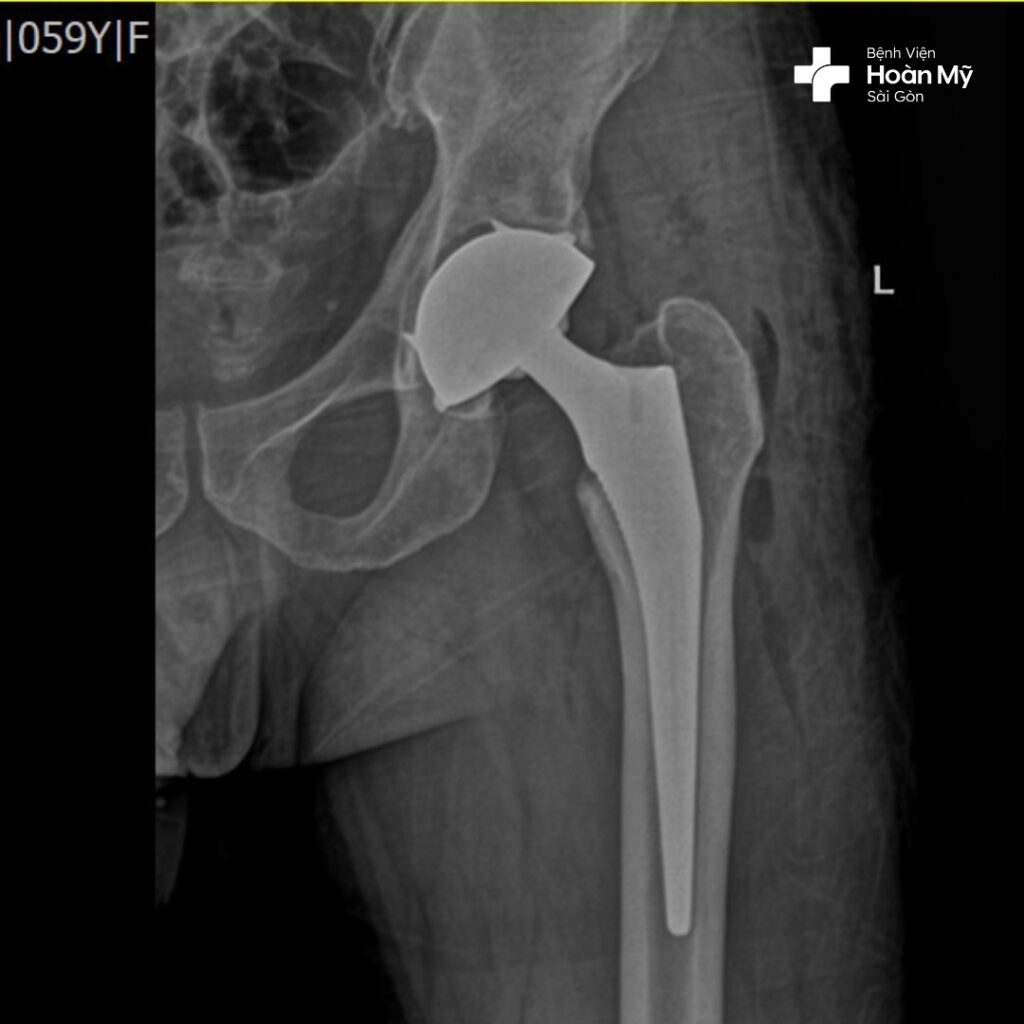

Hình ảnh X-quang sau phẫu thuật thay khớp háng của ông Đ.

Kỹ thuật thay khớp háng cùng lúc giúp ông Đ. giải quyết triệt để tình trạng hoại tử chỏm xương đùi với duy nhất một lần phẫu thuật. Điều này không những giúp tiết kiệm về mặt thời gian, khi người bệnh không phải đối mặt với hai lần phẫu thuật (thông thường lần phẫu thuật thứ hai phải cách lần phẫu thuật đầu tiên ít nhất 1-2 tháng), đồng thời tiết kiệm chi phí điều trị, giúp tâm lí người bệnh ổn định và lạc quan hơn.